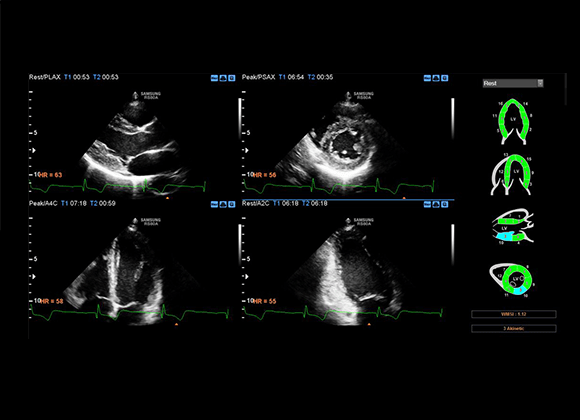

RS80A with Prestige

Designed for Cardiovascular Disease

Equipped with Samsung's proprietary solutions such as S-3D Arterial Analysis, Strain+ and Stress Echo, RS80A with Prestige helps to measure artery plaque volume for quantitative analysis purpose and track morphological changes, while detecting functional changes of vessels

Strain+

Strain quantitatively displays a Bull's Eye which shows left ventricular motion and dyssynchrony at a glance.

Stress Echo

The Stress Echo package includes wall motion scoring and reporting. It includes exercise Stress Echo, pharmacologic Stress Echo, diastolic Stress Echo and free programmable Stress Echo.